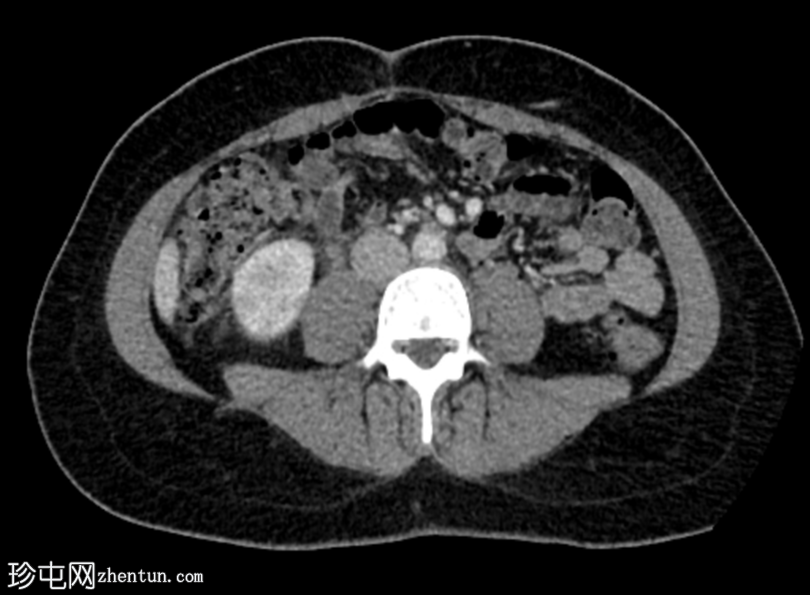

轴位增强扫描(门静脉期)

右肾在轴位和冠状位图像上均可见多个楔形低强化区,伴有轻度肾周脂肪间隙模糊。

双侧肾盂及输尿管轻度壁增厚和强化。

膀胱壁轻度增厚。

影像

学表现提示右侧急性肾盂肾炎和左侧肾盂及输尿管炎。

该病例具有典型的急性肾盂肾炎特征,表现为右肾实质楔形低密度区,双侧肾盂及输尿管壁增厚和强化。实验室检查发现尿液分析中有白细胞和脓细胞,尿培养中检测到大肠杆菌。